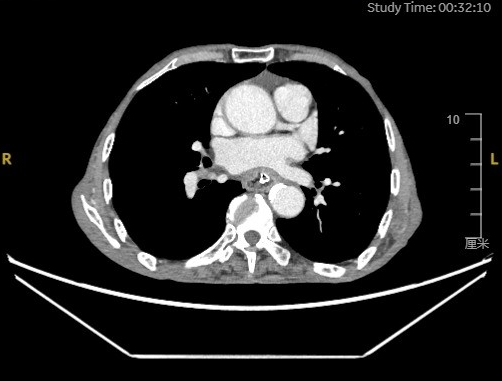

家住临沂市兰陵县的刘爷爷不慎误吞鸡脖,连续4天尝试多种办法始终无法自行取出,已出现吞咽困难及胸痛症状,紧急前往当地医院就诊。CT检查显示,患者食管内异物周围可见气体,考虑为食管壁损伤,且异物位置紧邻左心房,取出风险极高,当地医院建议立即转入上级医院进一步治疗,家属连夜驱车数百里来到青大附院西海岸院区。

急诊科、耳鼻咽喉科值班医师接诊后,迅速启动应急处置流程,立即联系消化内科会诊。崔铭娟副主任医师第一时间进行会诊,面对百岁高龄、基础情况复杂的患者,她深知实施内镜手术的高风险,操作稍有不慎,易引发食管穿孔、大出血、纵隔感染等严重并发症,危及患者生命。“年龄绝不是放弃治疗的理由。越是高龄患者,我们越要全力以赴。”崔铭娟耐心安抚患者与家属情绪。经放射科团队紧急CT检查,发现异物已部分嵌入食管壁,最薄处仅剩3毫米。在精准评估异物位置、与邻近组织的关系及手术风险后,崔铭娟果断确定治疗方案,决定为患者实施急诊内镜下异物取出术。